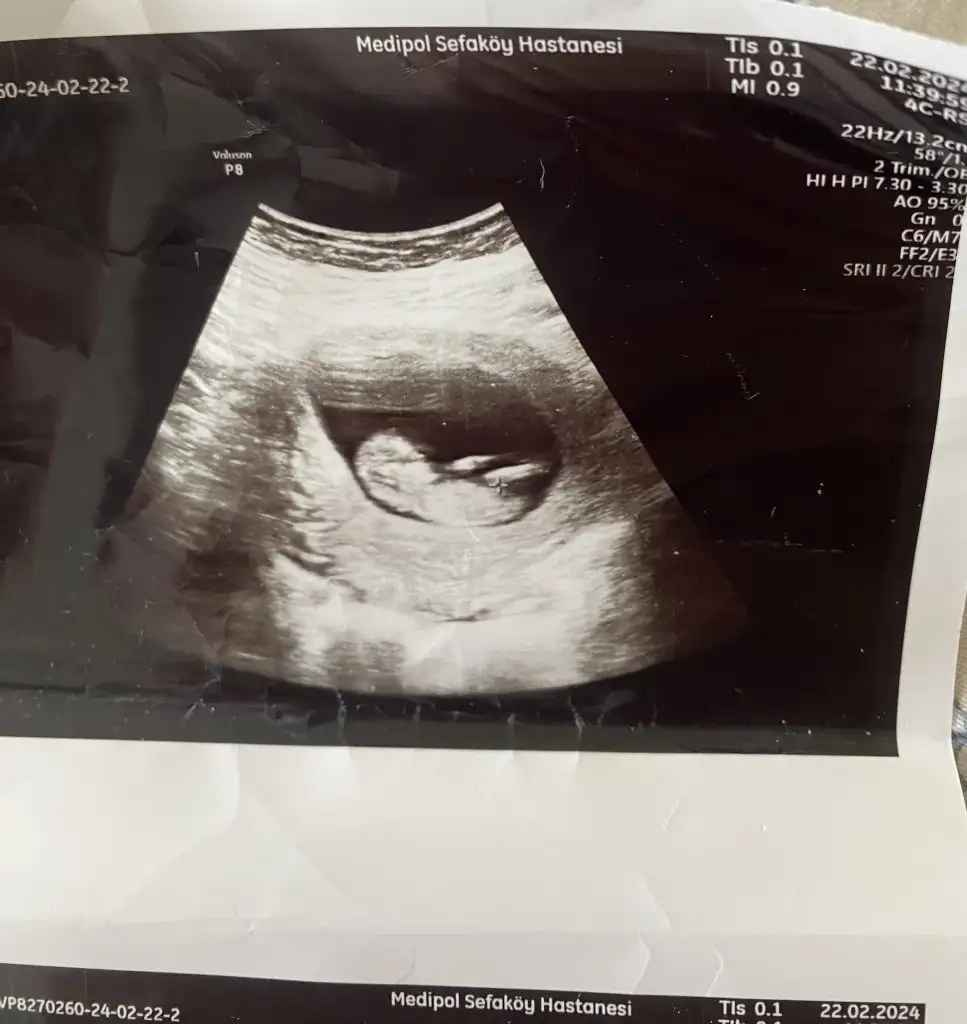

Bu da benimki 14+4 olduk bir bakın kızlar sizce ne doktor belli değil dedi henüz. Bir başka doktor da erkek gibi duruyor dedi bilemedik valaKızlar bebişlerinizin ultrason resimlerini ve cinsiyetini kaçıncı haftada olduklarını yazında kendi ultrason resimlerimizle kıyaslayıp fikirde bulunalım. Nub teorisi, kafa şekli, kemik yapısından cinsiyet teorileri tutuyor mu bakalım bir